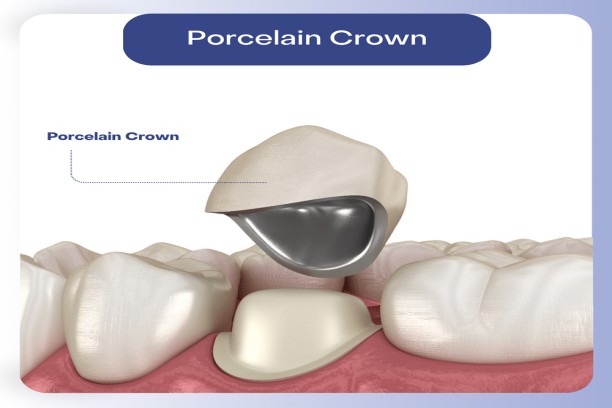

Ceramic Crowns

Tooth-colored crowns that restore strength and natural appearance